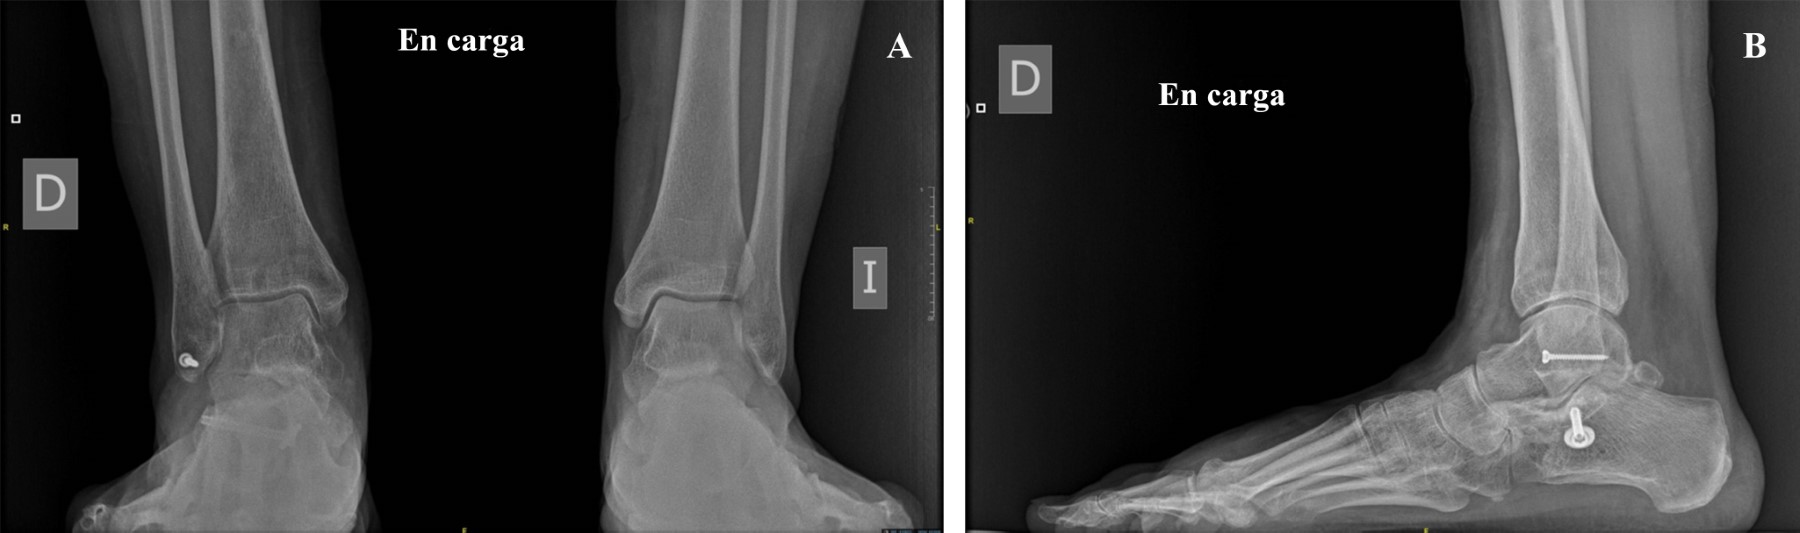

Introduction: subtalar dislocations, typical of high-energy trauma, are classified as medial, lateral, anterior or posterior depending on the deviation of the foot in relation to the talus. Lateral dislocation accounts for 17% of the total and has a worse prognosis. Immediate reduction is required to reduce the risk of sequelae, the incidence of which is around 90%. Objective: a case of lateral subtalar dislocation is presented; a review of the literature on its diagnosis, treatment and prognosis is carried out. Clinical case: a 46-year-old woman fell from a height of 3 meters, with severe deformity in the hindfoot. There was good distal vascular coloration, but no pulse or posterior tibial sensitivity could be identified. In addition, she had a medial sulcocutaneous fold under the head of the talus. Plain radiograph and CT revealed lateral subtalar dislocation, with fracture of the sustentaculum tali, and a "fleck sign" in the posterior region of the distal fibula. Suspecting soft tissue incarceration, a medial approach was performed, observing interposition of the posterior tibial neurovascular bundle. After joint reduction, the sustentaculum tali and the "fleck sign" were osteosynthesized. In addition, a complete section of the long lateral peroneal tendon was identified, which was tenodesed to the short peroneal tendon. Finally, an external fixator was placed. After eight weeks, the fixator was removed and weight bearing was authorized; after six months, mobility was complete and hypoesthesia persisted only in the plantar pad. Conclusions: lateral subtalar dislocation is an uncommon entity with a poor prognosis. Adequate interpretation through a thorough examination and pre-reduction CT of the bone and soft tissue lesions minimizes future sequelae.

Figure 6

Figure 7